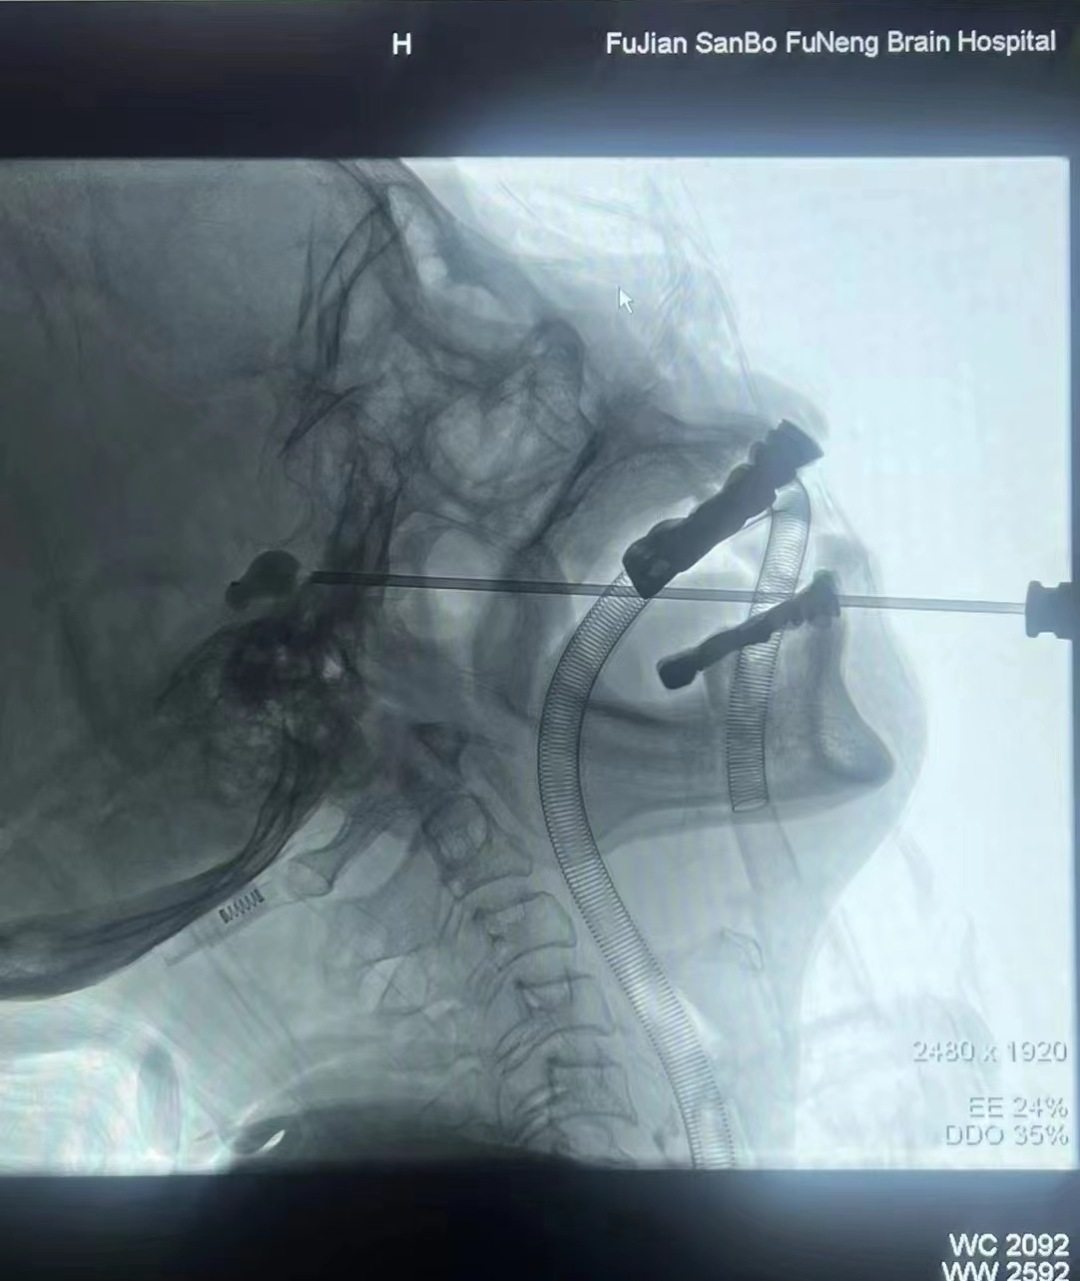

微球囊压迫术治疗三叉神经痛。

过去针对三叉神经痛治疗,往往采用传统开颅手术方式,风险大,康复周期长。现今,张朋及其团队采用国内先进的微创术式——微球囊压迫术,用小小球囊来解决“疼痛之王”。

手术开始,张朋先在李女士的嘴角侧开个针眼大小的创口,随后熟练地运用微球囊将导致三叉神经痛的神经纤维压迫几分钟,阻断痛觉神经传导。10余分钟过后,手术结束,反复折磨李女士的爆发性疼痛消失了,她说话进食终于恢复如常。

张朋介绍,采用微球囊压迫术治疗,患者创伤小,恢复快,并发症少,可以说是“创口贴”手术。